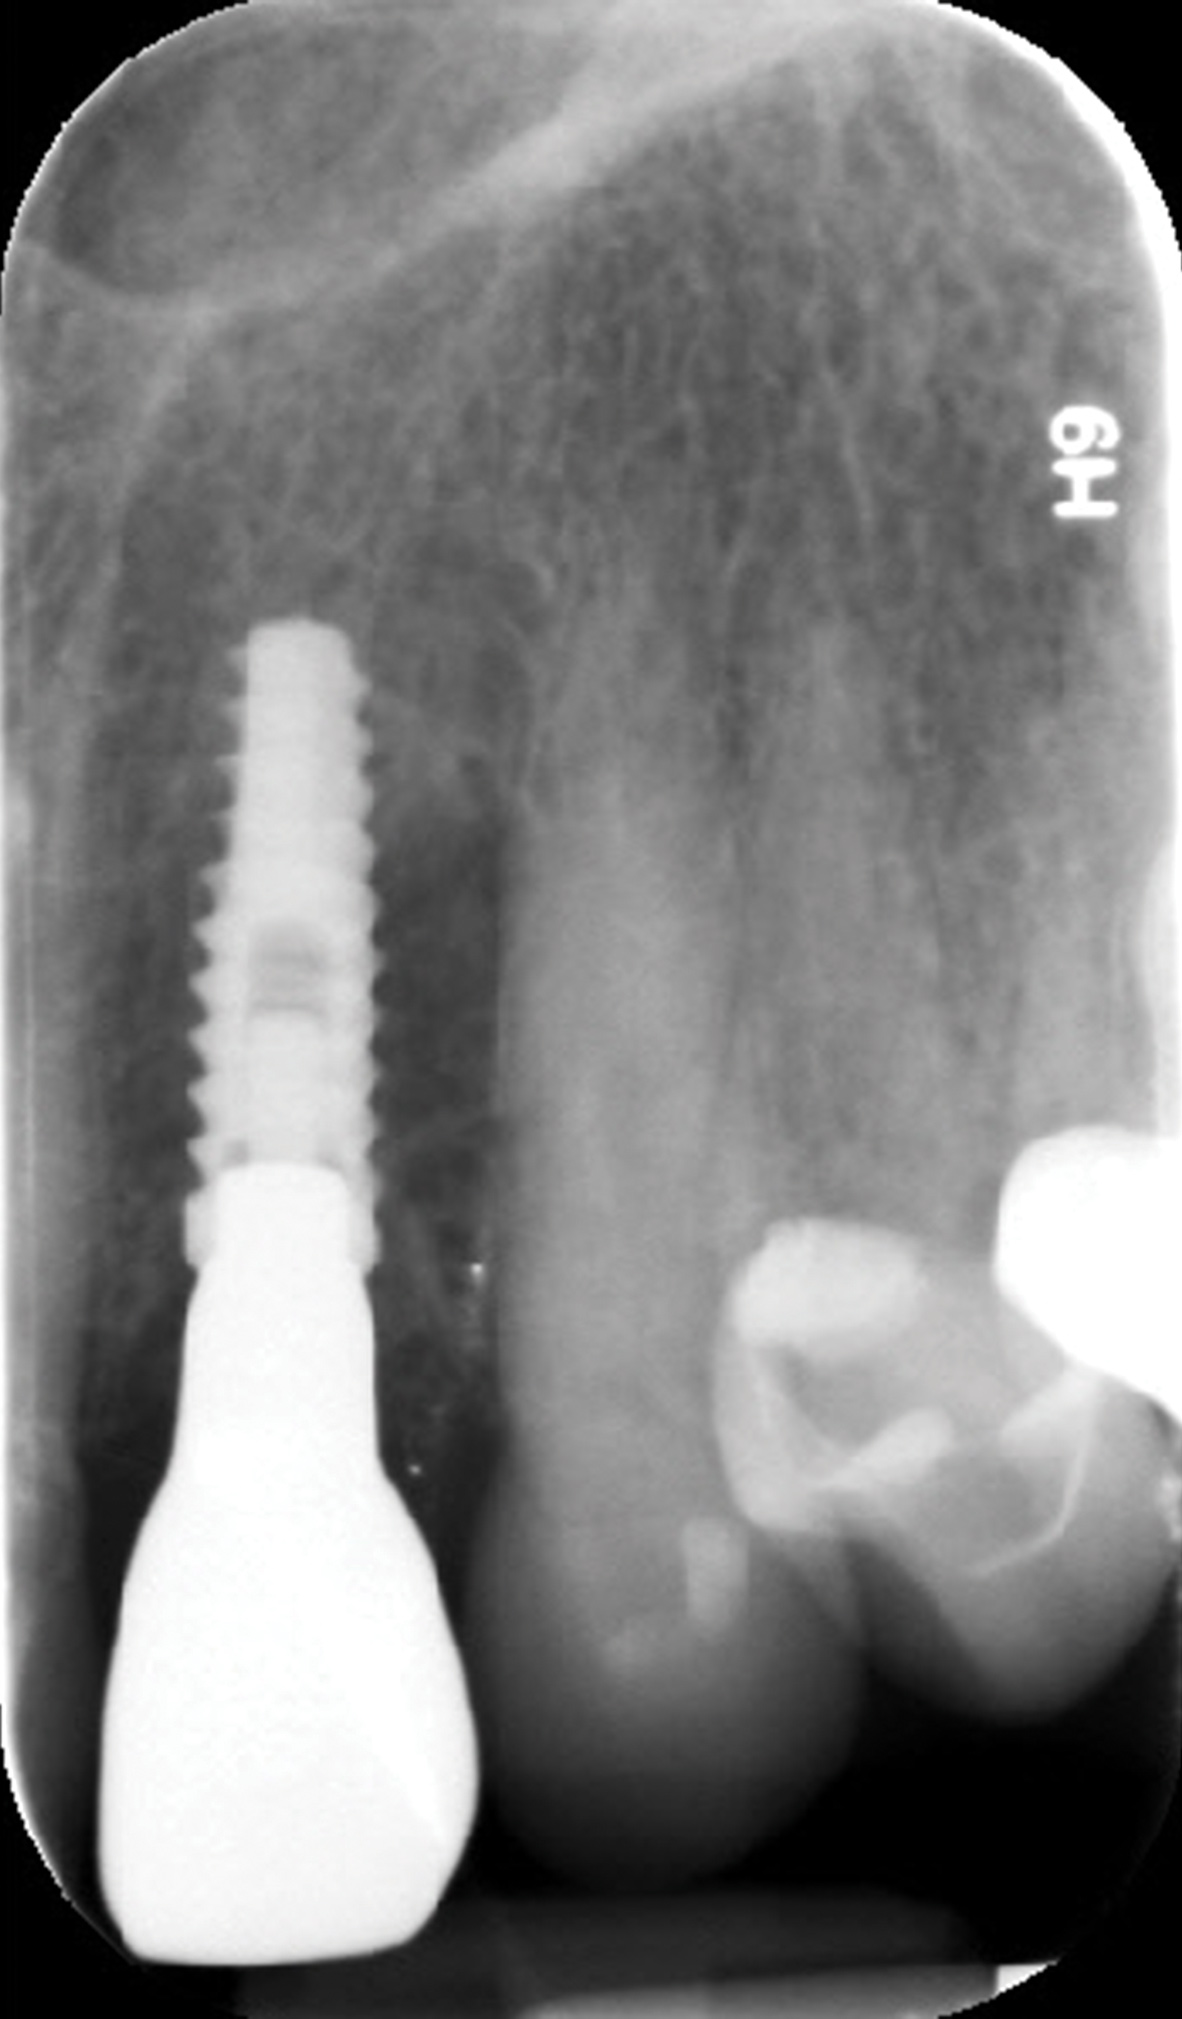

Implant insertion (5.5 mm x 13 mm NobelActive®, Nobel Biocare, nobelbiocare.com) gave excellent primary stability, was level with the residual buccal bone, and achieved an ISQ reading of 74 (Figure 14). Lingual bone contouring (to avoid abutment impingement) was followed with implant gap grafting, which included the mesiobuccal root defect and adjacent extraction site, using mineralized particulate cortico-cancellous allograft (enCore®, Osteogenics Biomedical). A 7 mm x 8 mm poly-ether-ether-ketone (PEEK) healing abutment was inserted and the access opening filled with PTFE tape (Figure 15). A single layer of dHACM (Figure 16) was inserted on the bone graft with tissue forceps and saturated with saline to seal the implant-soft-tissue interface. Suturing with 4-0 chromic gut secured the site, using inverse "figure 8" at the anterior and interrupted sutures at the posterior margin (Figure 17).

Fig 10. Periapical radiograph at 14 months restored.

Figure 10

Fig 14. Extraction site, with mesiobuccal bone dehiscence concealed under soft tissue, and immediate implant placement with ISQ post in position.

Figure 14